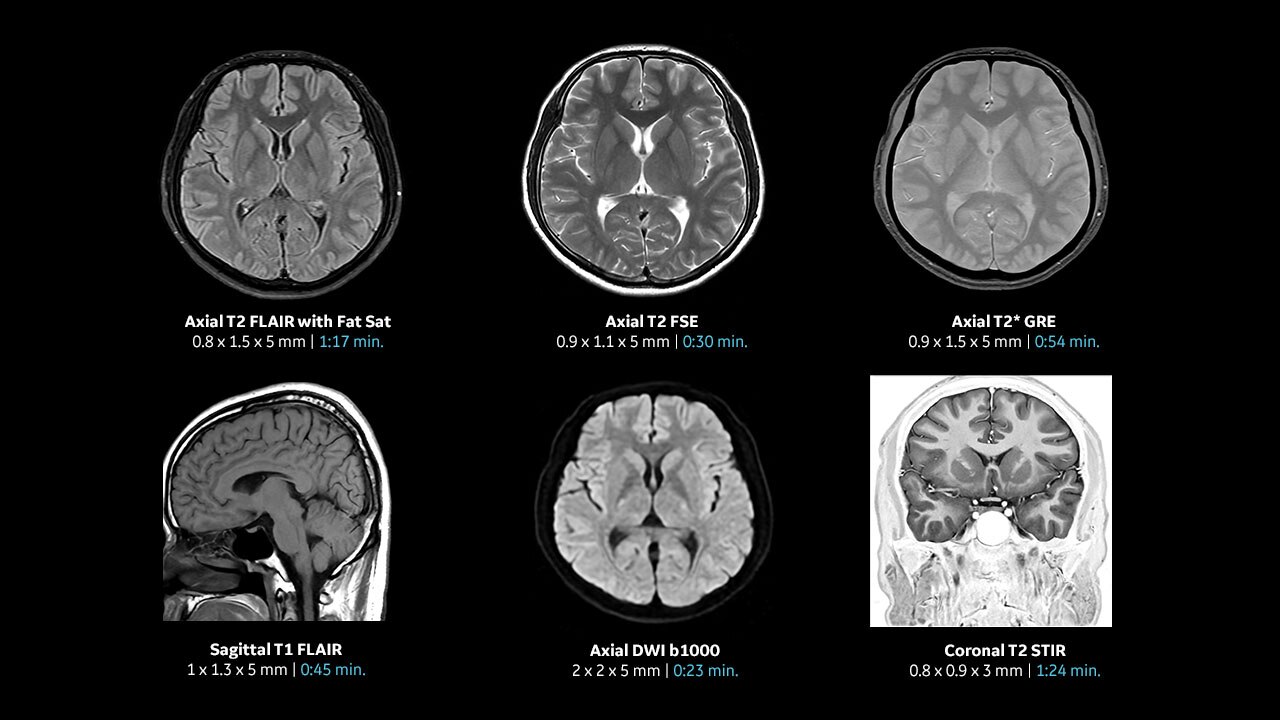

Con el acceso a la tecnología de IA avanzada más reciente, puede explorar todas las anatomías y obtener imágenes con una nitidez excepcional. Nuestro innovador algoritmo de reconstrucción basado en el aprendizaje profundo AIR™ Recon DL acelera el tiempo de exploración y tranquiliza a los pacientes.

El gradiente mejorado de hasta 80 mT/m,

200 T/m/s proporciona resultados excepcionales de forma más rápida y, con 146 canales de RF, puede garantizar la uniformidad de cada resultado.